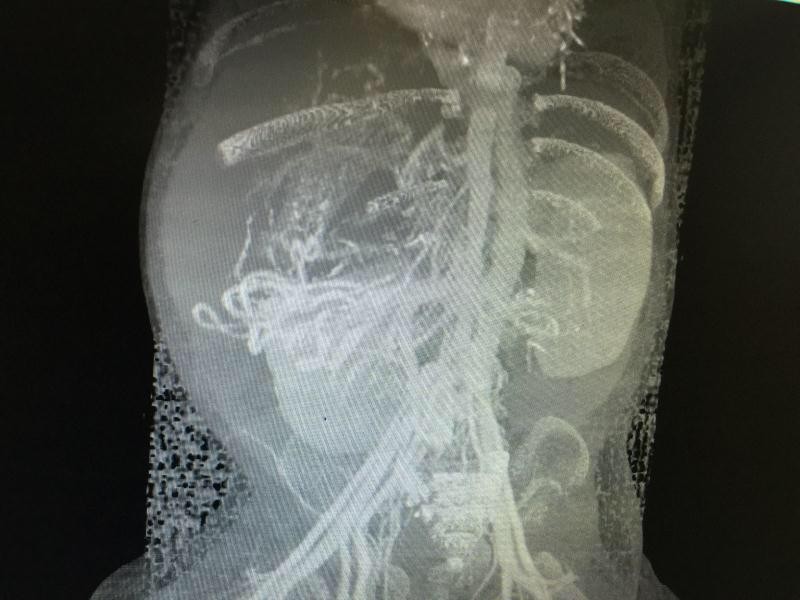

▲男嬰臟器全都「倒頭栽」 。(圖/翻攝自廣州日報,下同)

新生兒都是父母手掌心的寶貝,廣州一名9個月大的男嬰,出生後黃疸持續不退,後來全身泛黃黑,肚子脹大,原以為只是單純的膽道閉鎖,一經中山醫院檢查,才發現他的「臟器異位」,且從上到下全都顛倒,連接肝臟的腹主動脈和下腔靜脈的位置也長反,不僅如此就連脾臟都比一般人多6個。

男嬰(化名為垚垚ㄧㄠˊ)出生兩個月黃疸還是持續不退,不僅全身蠟黃,還被醫院診斷為「膽道閉鎖」,由於確診較晚,只能利用葛西手術把膽汁排進腸道,但無法根治膽道閉鎖問題。進一步檢查後,垚垚的臟器全都上下顛倒,包括肝、脾、胃、胰,連接肝臟的腹主動脈和下腔靜脈的位置也長反,除此之外,胰臟還多了6個。